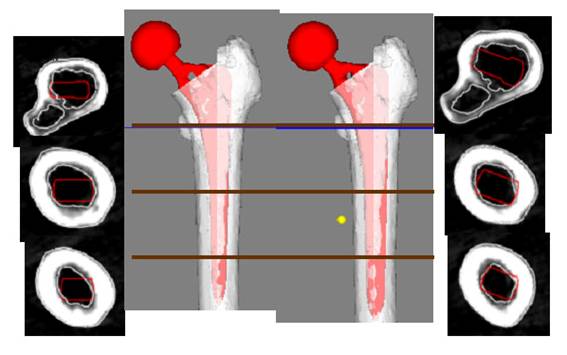

52歳 女性 両側変形性股関節症

![]() |

| 手術時間 | 83分 |

| インプラント |

|

| 設置精度 |